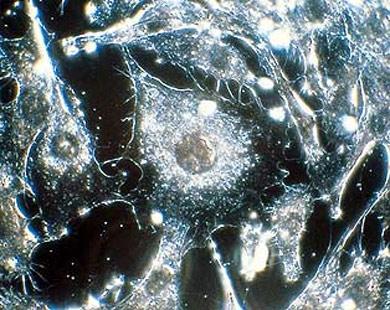

استخدم فريق من الباحثين الأمريكيين فى جامعة بنسيلفانيا الأمريكية تقنية حديثة تعتمد على موتورات معدنية متناهية الصغر لتدمير الخلايا السرطانية.